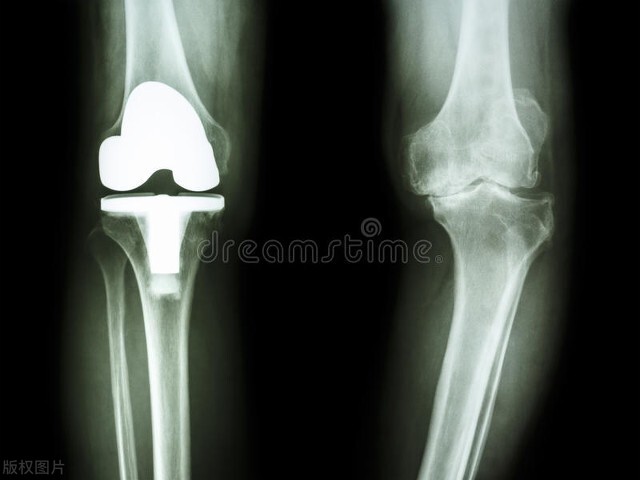

人老先老腿。随着右膝关节的病变,我不得不接受人工关节置换手术。